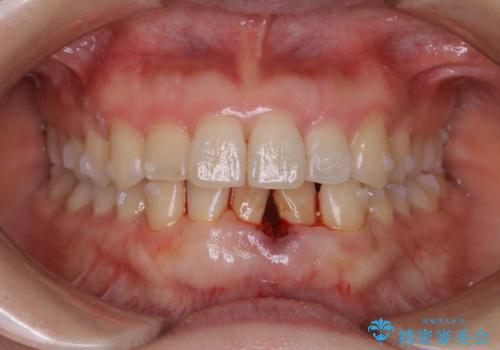

インビザライン・ライトでの抜歯矯正治療 (スリーインサイザー仕上げ)

- 上下の前歯のがたつきが気になるとのことで来院されました。最短治療とインビザラインでの矯正治療をご希望されました。

前歯のがたつきを無くすためには、スペースを確保する必要があります。上の前歯のがたつきは軽度ながたつきのため、歯と歯の間を研磨をして、そのスペースを使い並べていきます。下の前歯は、1本前歯を抜いて研磨せずに、その抜歯したスペースを使い並べることになりました。

インビザライン・ライトにて矯正治療を行うことになりました。

下の前歯は、スリーインサイザー仕上げと言って、通常前歯は4本ありますが(犬歯はいれていない)、そのどれか1本を抜歯して前歯を3本にして矯正治療を行うことを言います。また、先天的に歯の本数が少ない方もいますので、矯正治療を行っていなくても元々スリーインサイザーの方もいます。